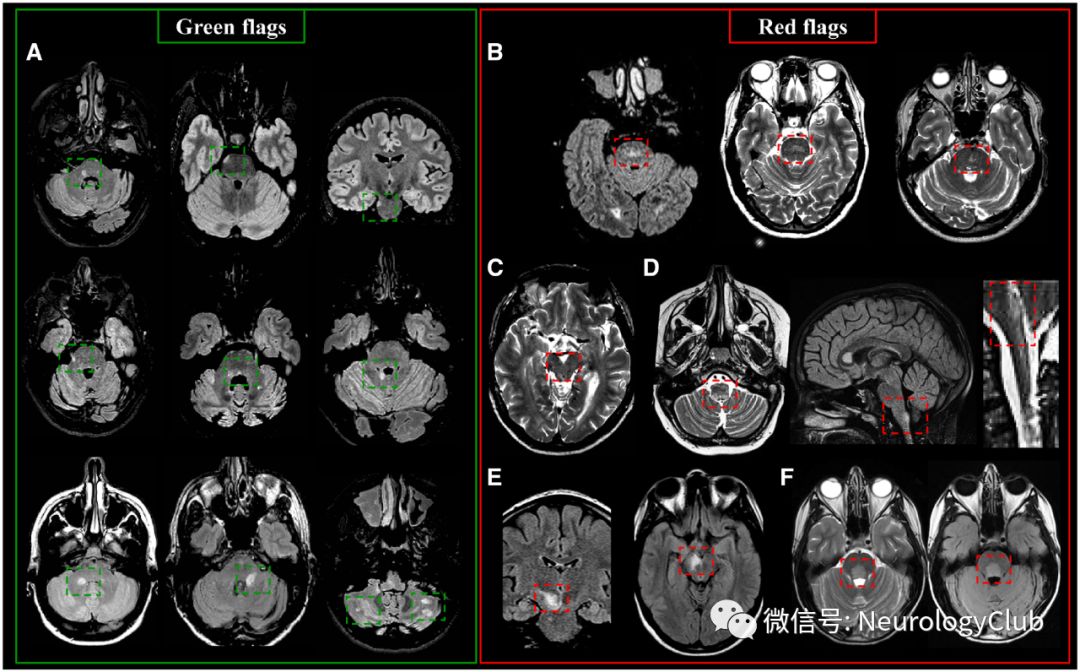

MS病灶通常分布在两个半球,早期多为轻度不对称性。病灶可见于中枢神经系统任何部位,相对于其他引发白质病变的疾病而言,MS常累及特定的白质区域,如脑室周围、皮质下白质、胼胝体、幕下(尤其是脑桥和小脑)和脊髓(尤其是颈段)。MS典型病灶(绿旗征)与非典型病灶(红旗征)见表2,相关影像学描述见图1-5。

图4:MS患者脊髓典型和非典型病灶以及不应该计数在内的病灶;左上:绿旗征:(A)矢状位短时间反转恢复序列上颈、胸髓病灶;(B)3T-T1WI上可见颈髓低信号(绿箭头);(C)T2WI和相位敏感 反转恢复序列可见颈髓病灶累及侧柱和中央灰质(绿箭);右上:(D)弥漫性脊髓病变,边界不清,不符合脊髓病灶的定义;底部:红旗征:(E)见于NMOSD的纵向广泛性脊髓受累,病灶范围在3个节段以上;(F)见于神经结节病的纵向广泛性脊髓受累,病灶范围在3个节段以上,伴软脊膜和脊髓周围强化;(G)见于亚急性联合变性的广泛选择性侧柱和后柱受累;(H)脊髓空洞;(I)见于动静脉瘘的广泛性T2高信号病灶,从脊髓圆锥前部延伸,可见斑点状和扭曲强化;(J)见于亚急性缺血性脊髓病的胸髓前部高信号病灶,延伸累及两个以上椎体节段;(K)脊髓型颈椎病患者颈髓T2高信号病灶,可见“薄煎饼样”强化;SC=脊髓。